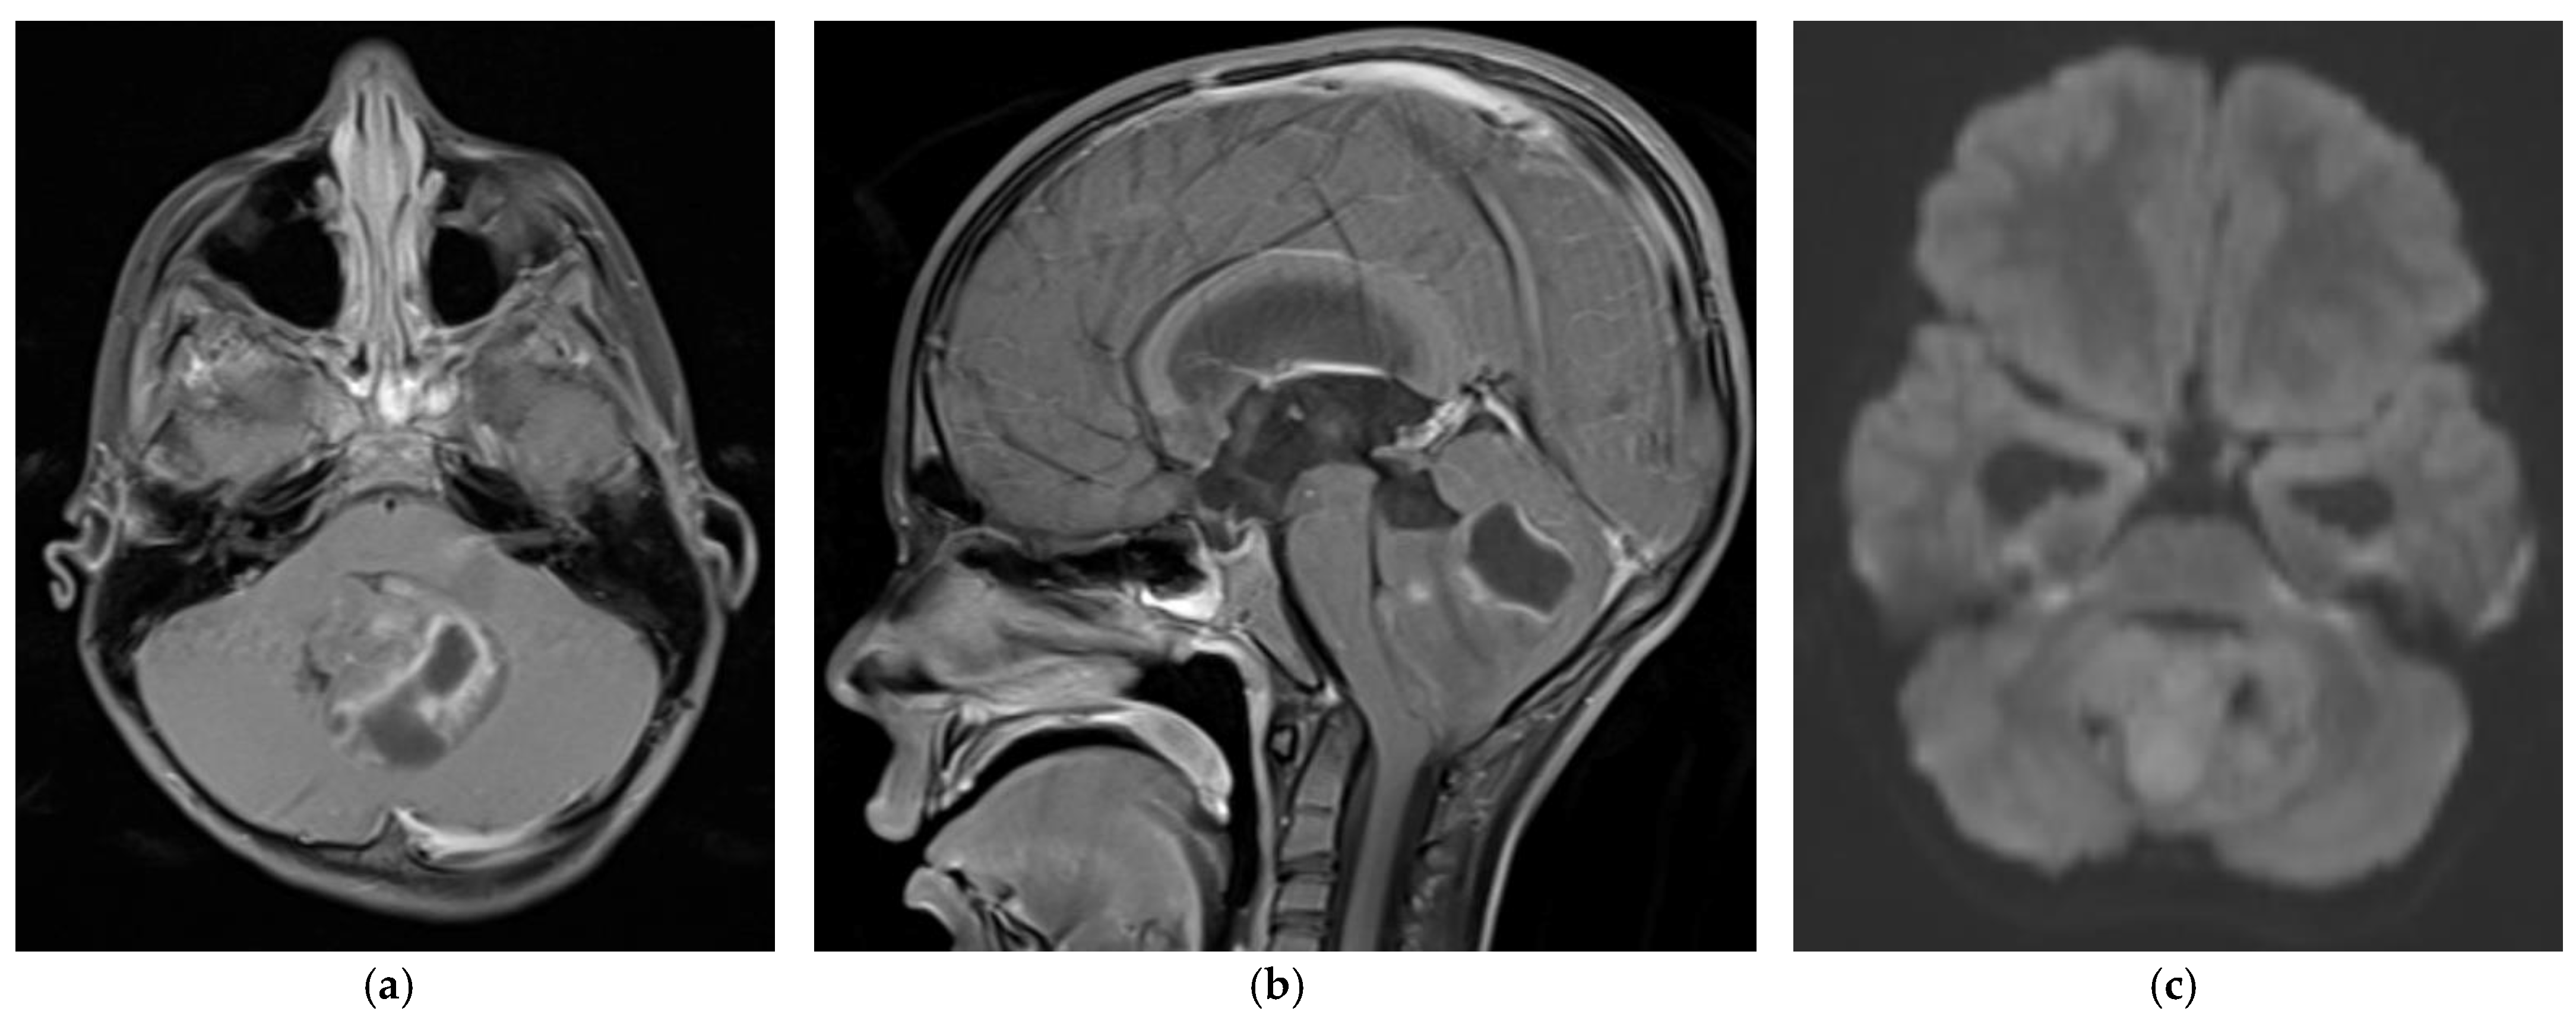

4.6. Imaging-Based Diagnosis

- Colafati, G.S.; Voicu, I.P.; Carducci, C.; Miele, E.; Carai, A.; Di Loreto, S.; Marrazzo, A.; Cacchione, A.; Cecinati, V.; Tornesello, A.; et al. MRI features as a helpful tool to predict the molecular subgroups of medulloblastoma: State of the art. Ther. Adv. Neurol. Disord. 2018, 11, 1756286418775375. [Google Scholar] [CrossRef]

- Perreault, S.; Ramaswamy, V.; Achrol, A.S.; Chao, K.; Liu, T.T.; Shih, D.; Remke, M.; Schubert, S.; Bouffet, E.; Fisher, P.G.; et al. MRI Surrogates for Molecular Subgroups of Medulloblastoma. Am. J. Neuroradiol. 2014, 35, 1263–1269. [Google Scholar] [CrossRef]

- Yeom, K.W.; Mobley, B.C.; Lober, R.M.; Andre, J.B.; Partap, S.; Vogel, H.; Barnes, P.D. Distinctive MRI features of pediatric medulloblastoma subtypes. AJR Am. J. Roentgenol. 2013, 200, 895–903. [Google Scholar] [CrossRef]